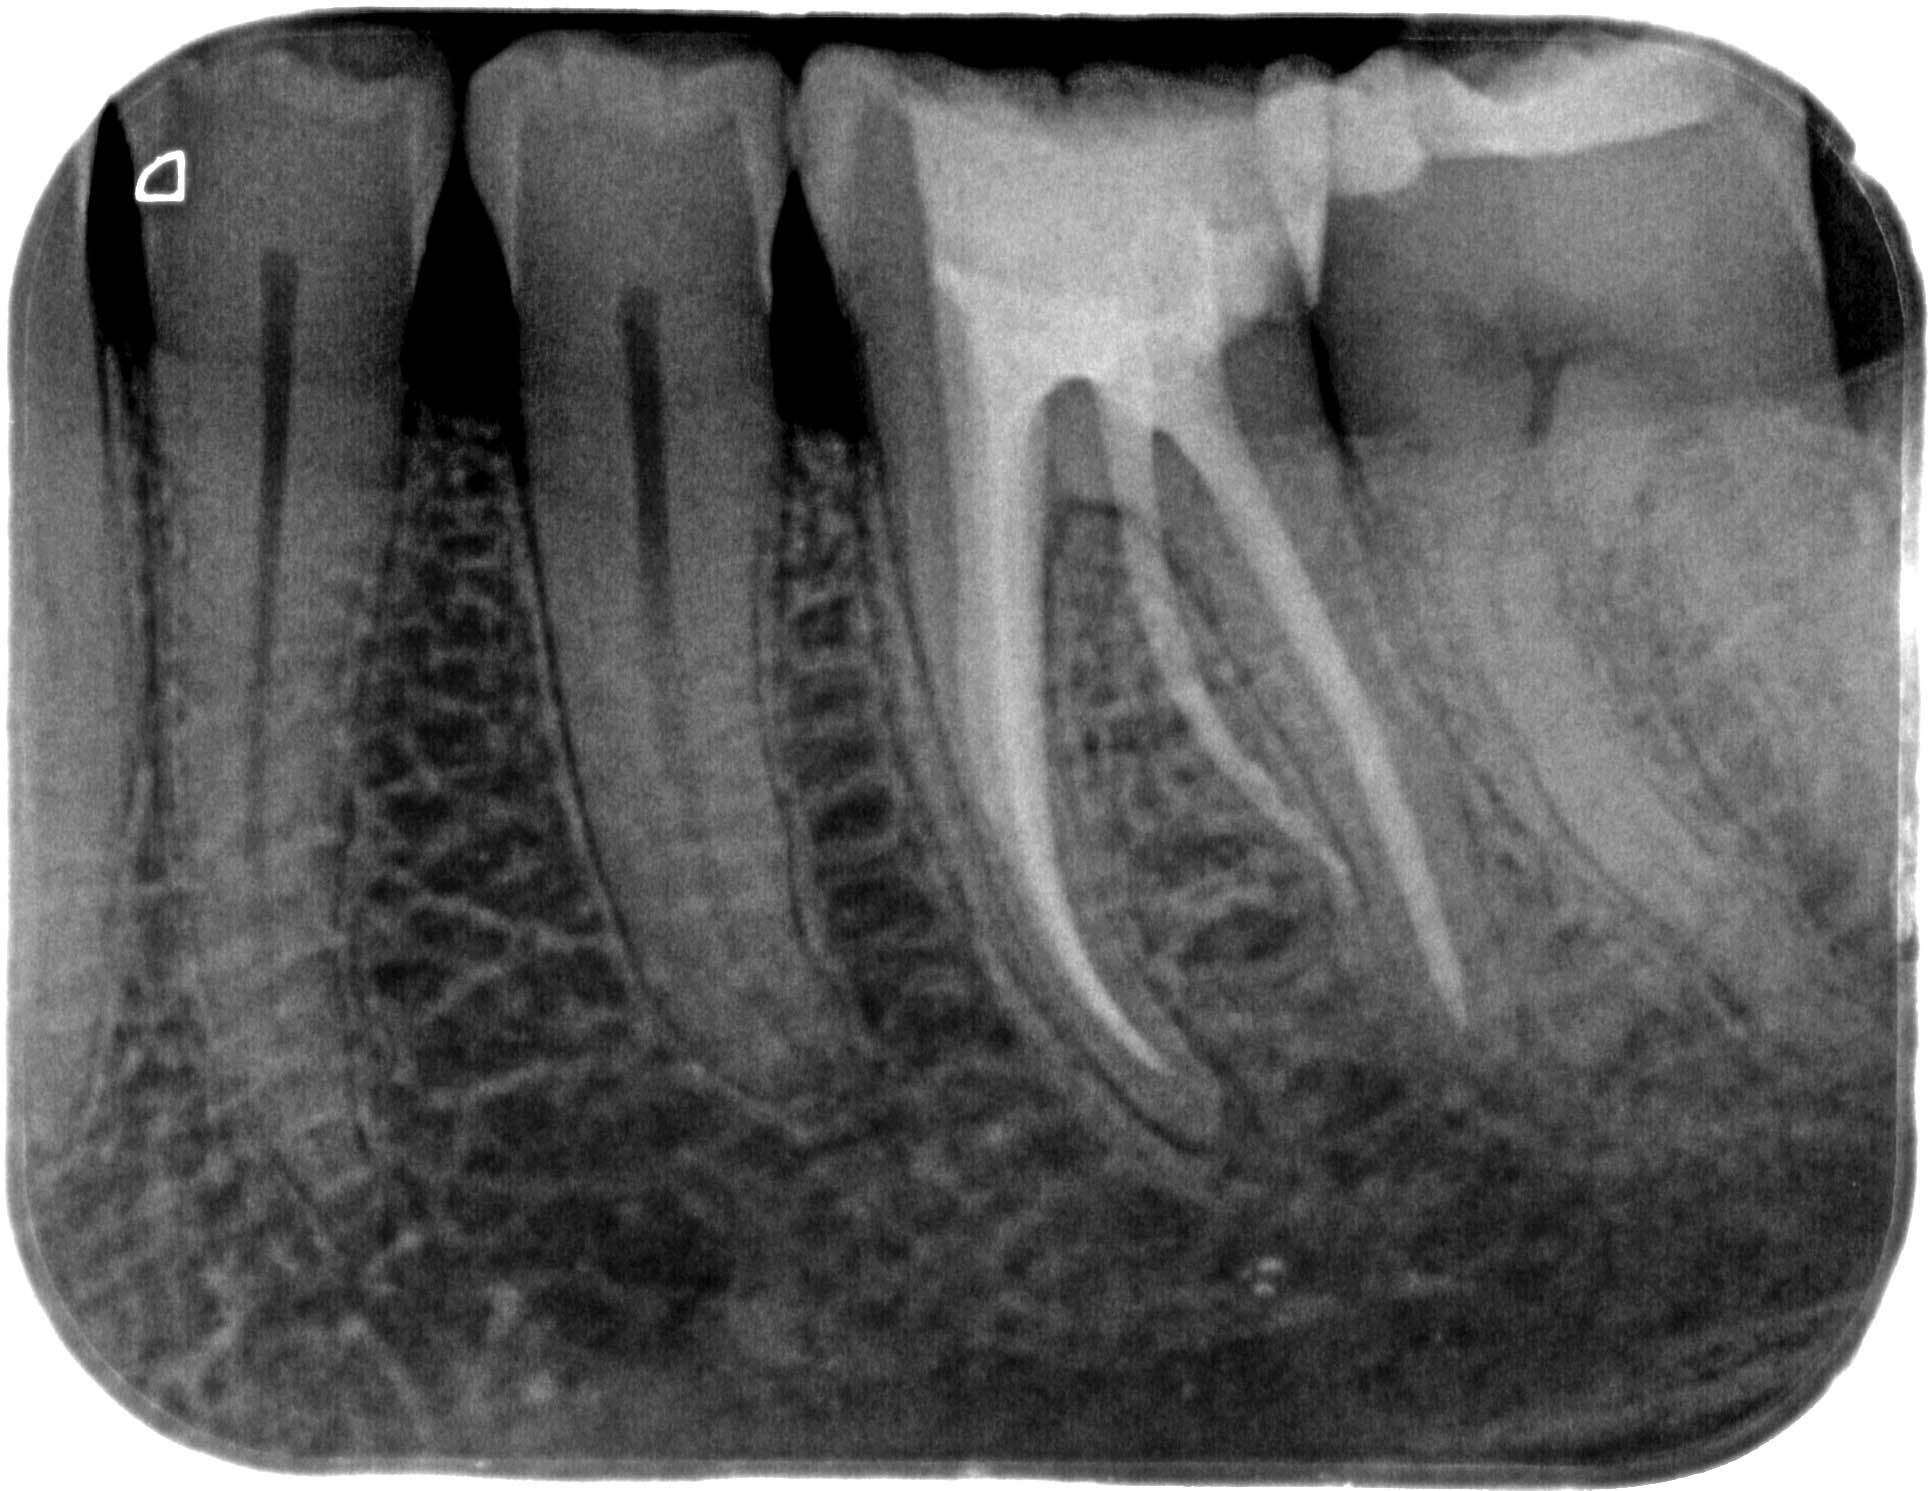

BF_36 (1 von 1)-2 Veröffentlicht 10. März 2014 am 1931 × 1491 in Wann ist ein DVT sinnvoll (3) – Zahn 36 mit radix entomolaris und Instrumentenfragmenten – Die WF Zahn 36- orthograde WF – Kontrollaufnahme